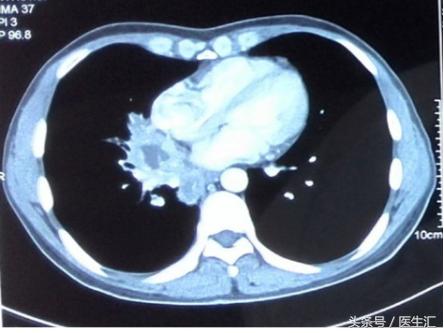

肺部CT示:

右肺门巨大占位,伴右肺门多发淋巴结肿大,怀疑“肺癌”,伴阻塞性肺炎;